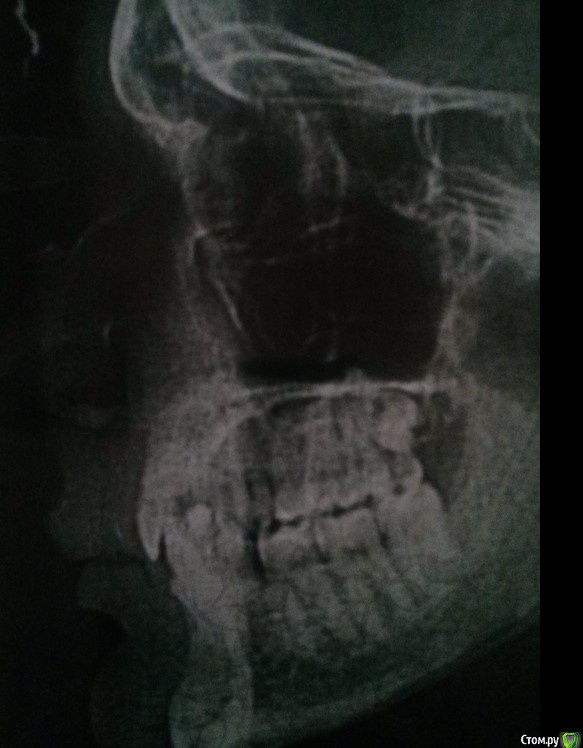

adentiyaHelp Опубликовано 29 марта, 2018 Автор Поделиться Опубликовано 29 марта, 2018 (изменено) Жалобы: проблемы с пережевыванием пищи, нет зуба в переди - как ходить - просто очень комплексую.Провел ортодонтическое лечение на нижней челюсти, поставил 2 импланта. Как протезировать дальше?Снимок 2018, после ортодонтического лечения нижней челюсти: http://prntscr.com/ixzbdh Изменено 29 марта, 2018 пользователем adentiyaHelp Ссылка на комментарий